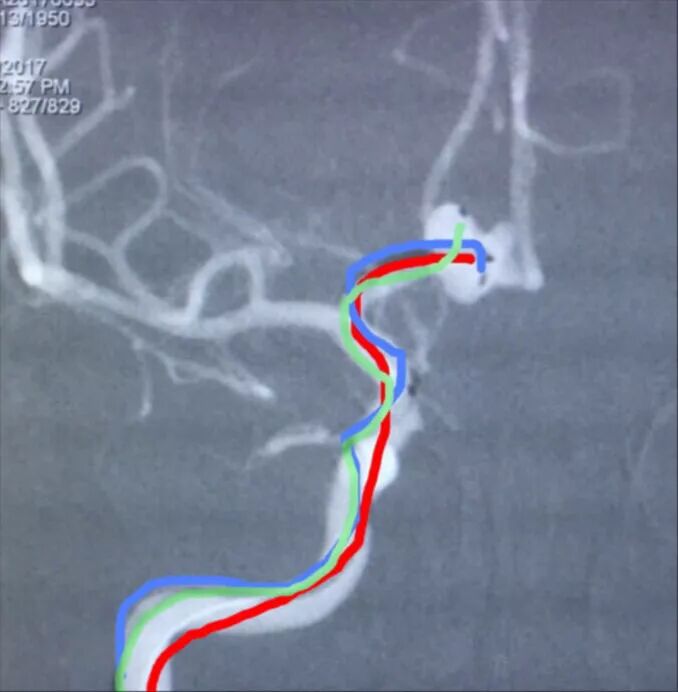

后交通动脉瘤,朝外下方生长,欲把微导管头塑成C形,需塑两个弯儿,第一个弯儿(蓝箭头)顺应动脉瘤体和颈内动脉C1段的成角,第二个弯儿(绿箭头)顺应颈内动脉虹吸弯前膝的弯度,更近心端的弯儿(黑箭头)不用塑形,是微导管在载瘤动脉内的自然成形

栓塞后的工作位造影和蒙片